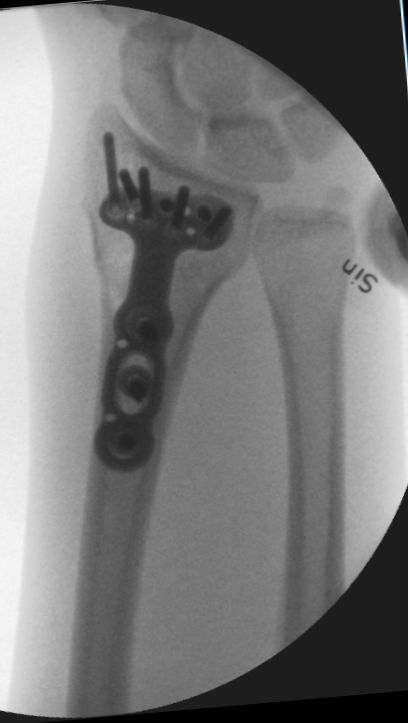

Välplacerad DVR-platta. Sidobilden är inte rak.